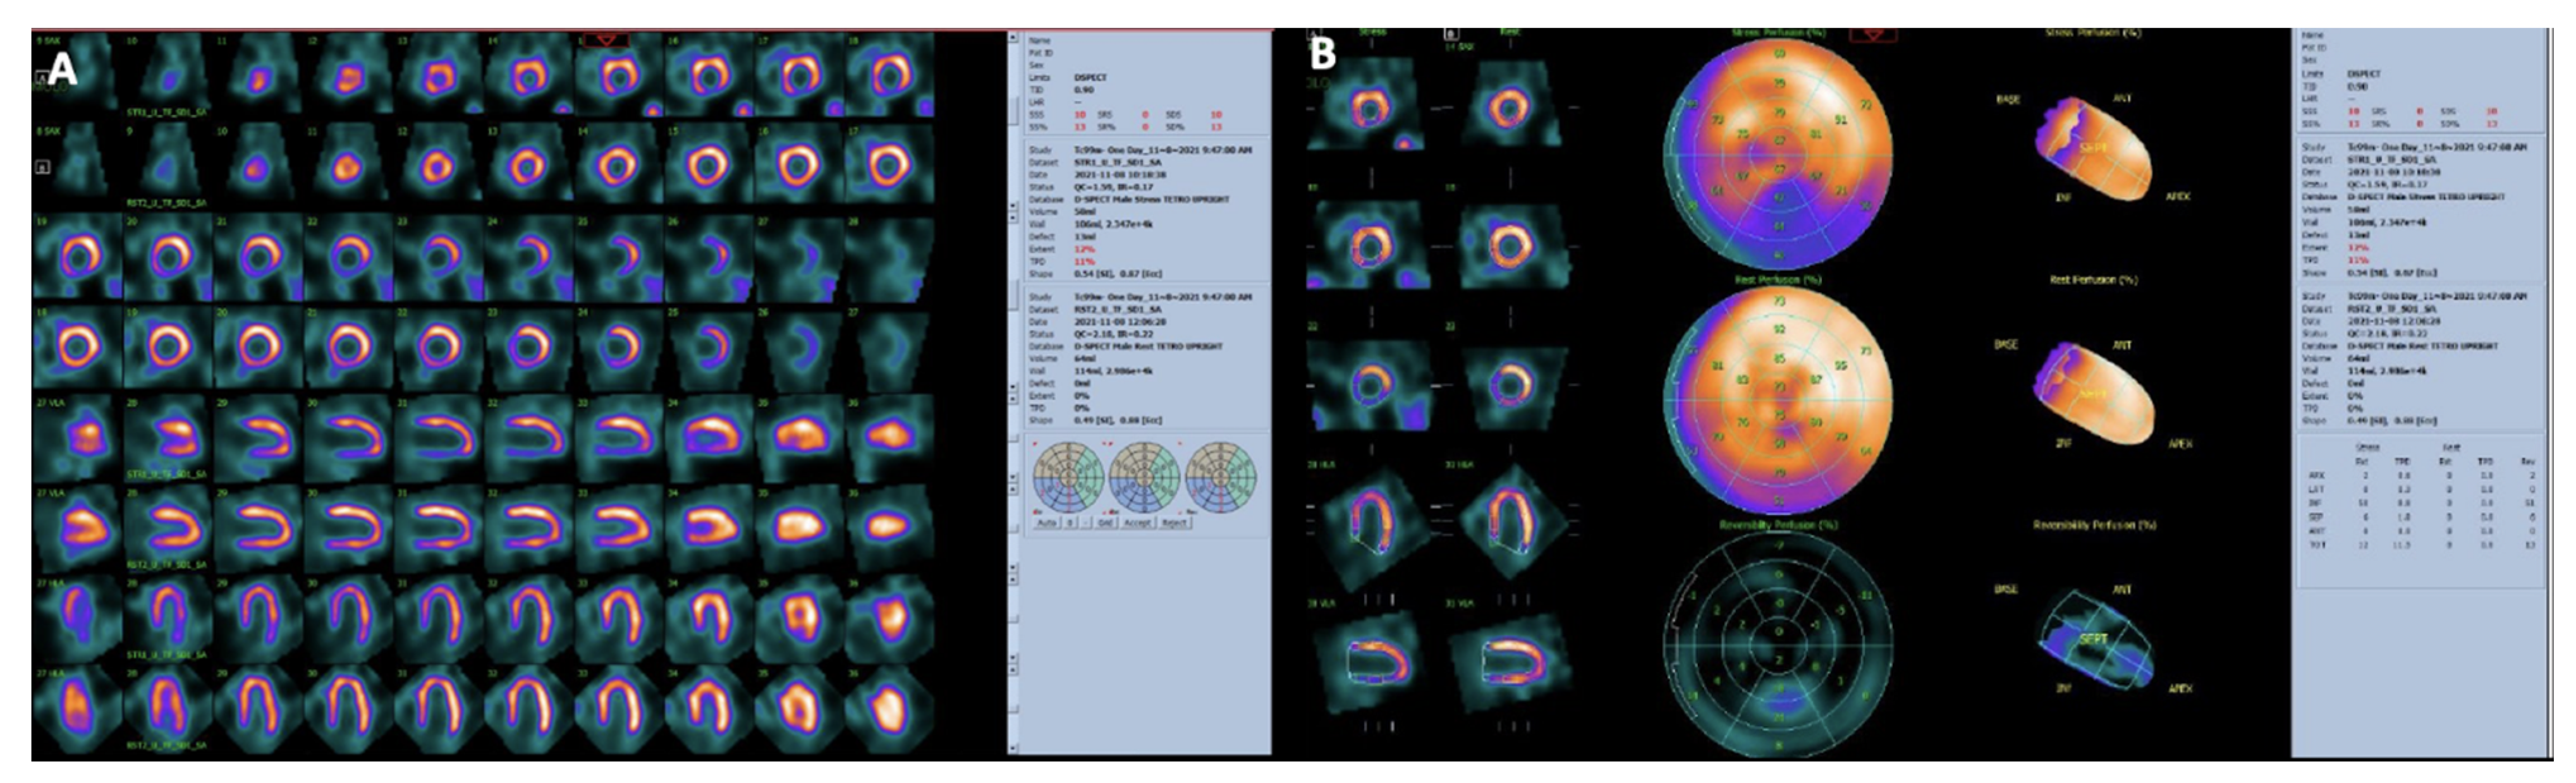

Figure 7.

Myocardial perfusion SPECT with Tc-99m-Tetrofosmin in a patient with CAD performed at stress (maximal cycloergometer exercise) and at rest. Stress and rest slices in three axes are shown in (Panel (A)). Polar maps under stress and at rest are shown in (Panel (B)). Slices and polar maps show a stress perfusion defect in the inferior wall which significantly improves (reverses) in the rest study. The pattern is typical of stress-induced myocardial ischemia.